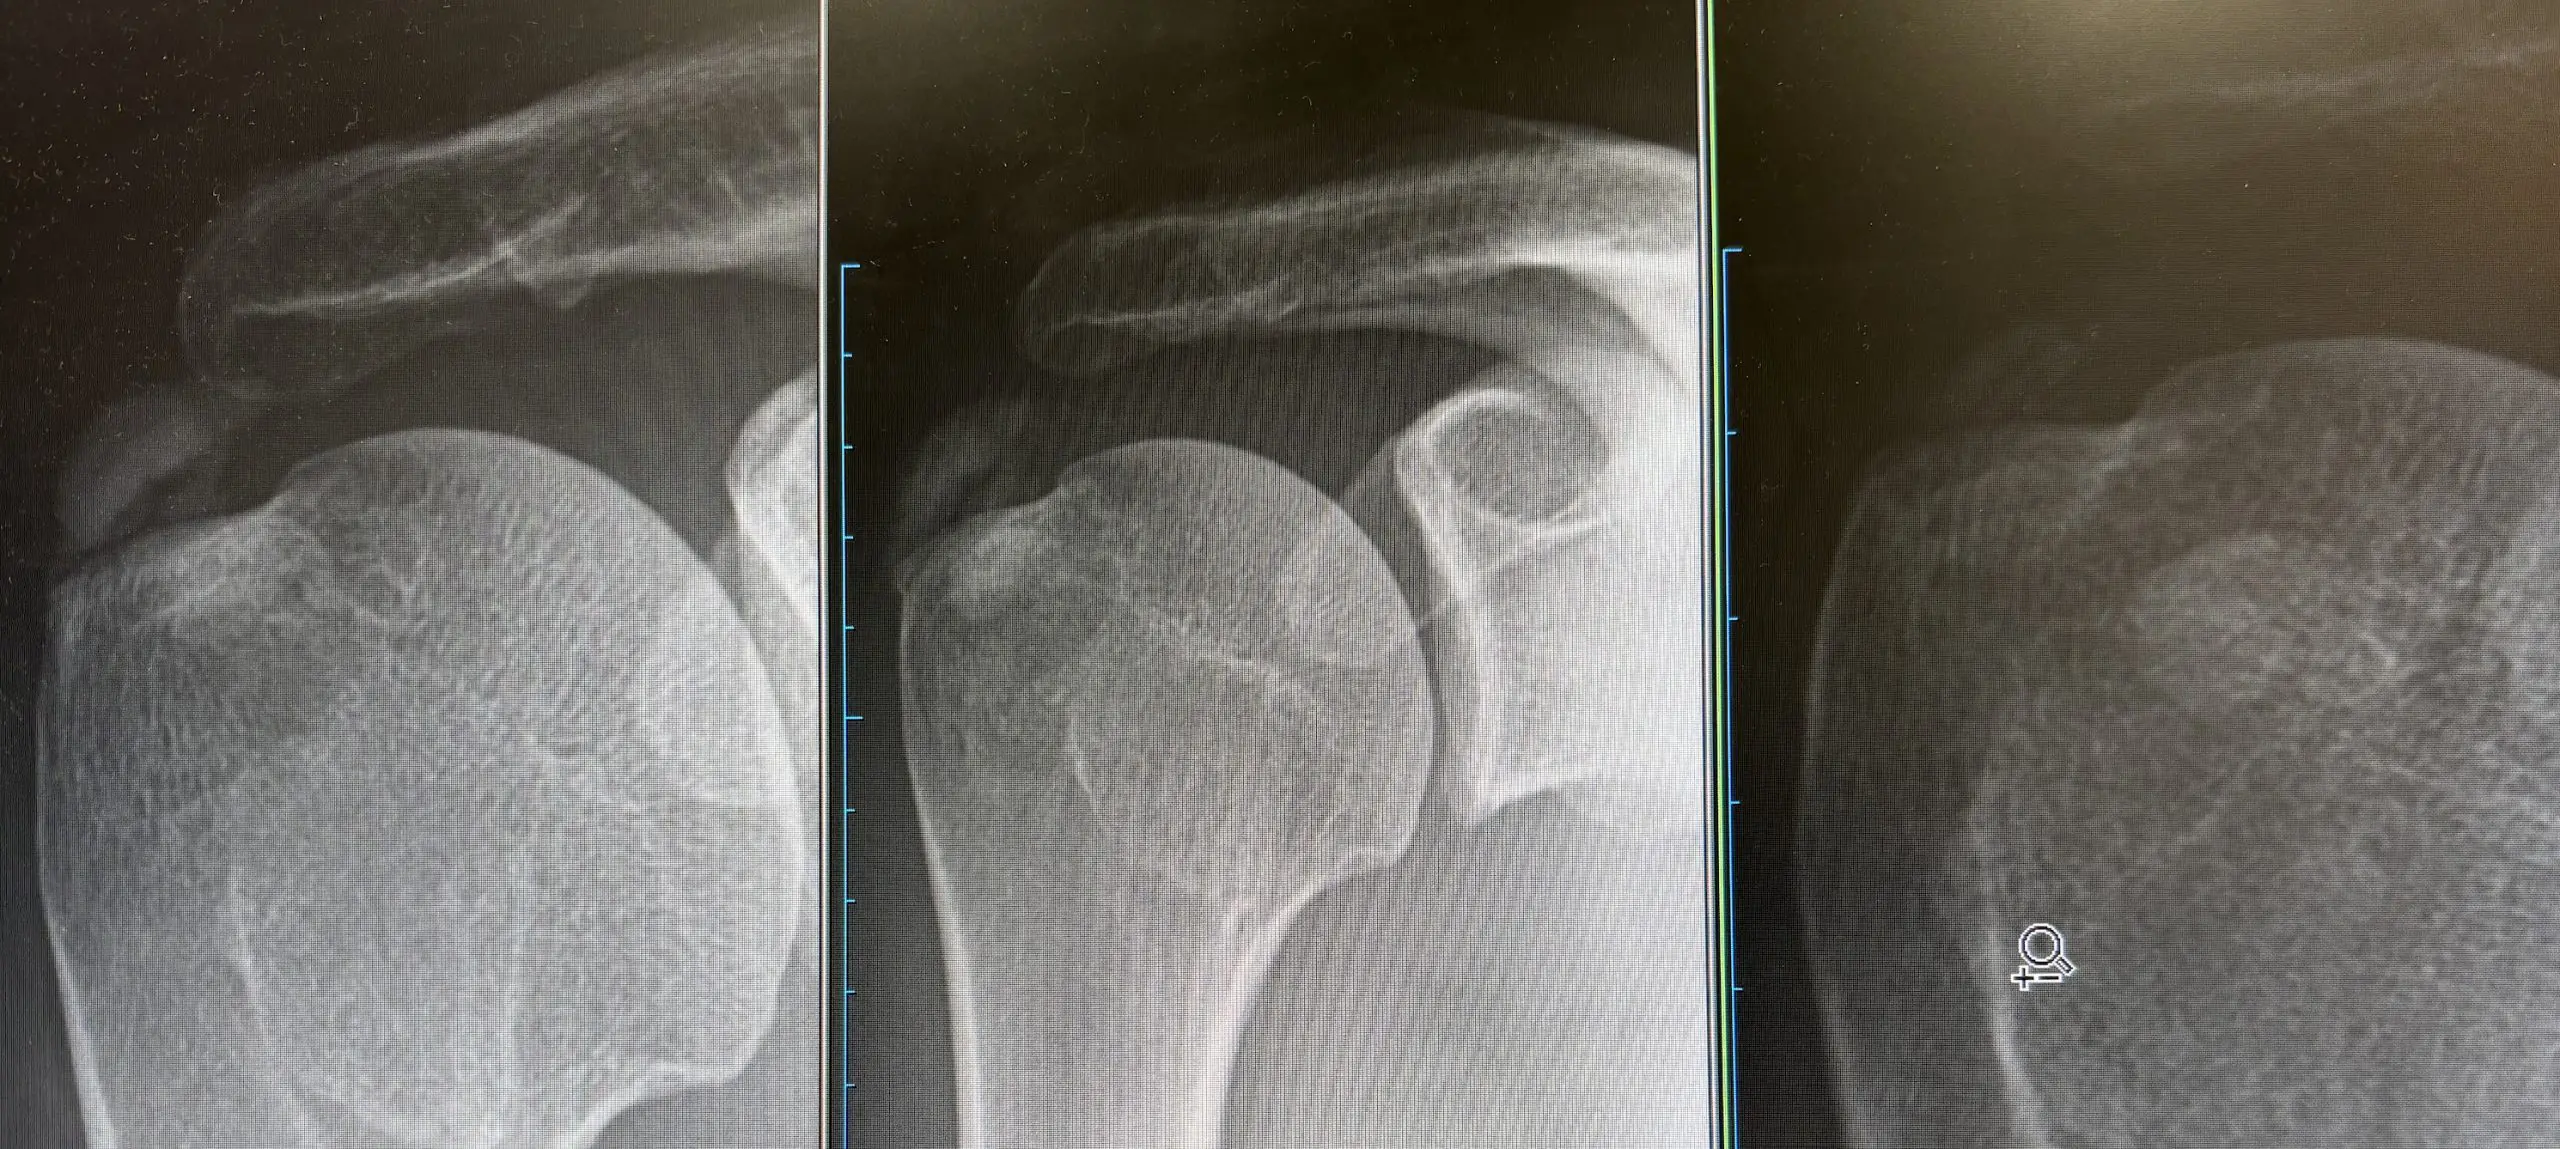

早速当院で肩関節の石灰化のある方に拡散型対外衝撃波を行ってみたところ、こんなに明らかに石灰がなくなりおったまげました。

1枚目は未治療、二枚目はパンピング後、三枚目は対外衝撃波後 パンピングは針を刺して石灰を壊して石灰を水圧で吸い上げる方法ですが、かなり残ってしまいました。それに対し体外衝撃波はではほとんど石灰は残りませんでした。